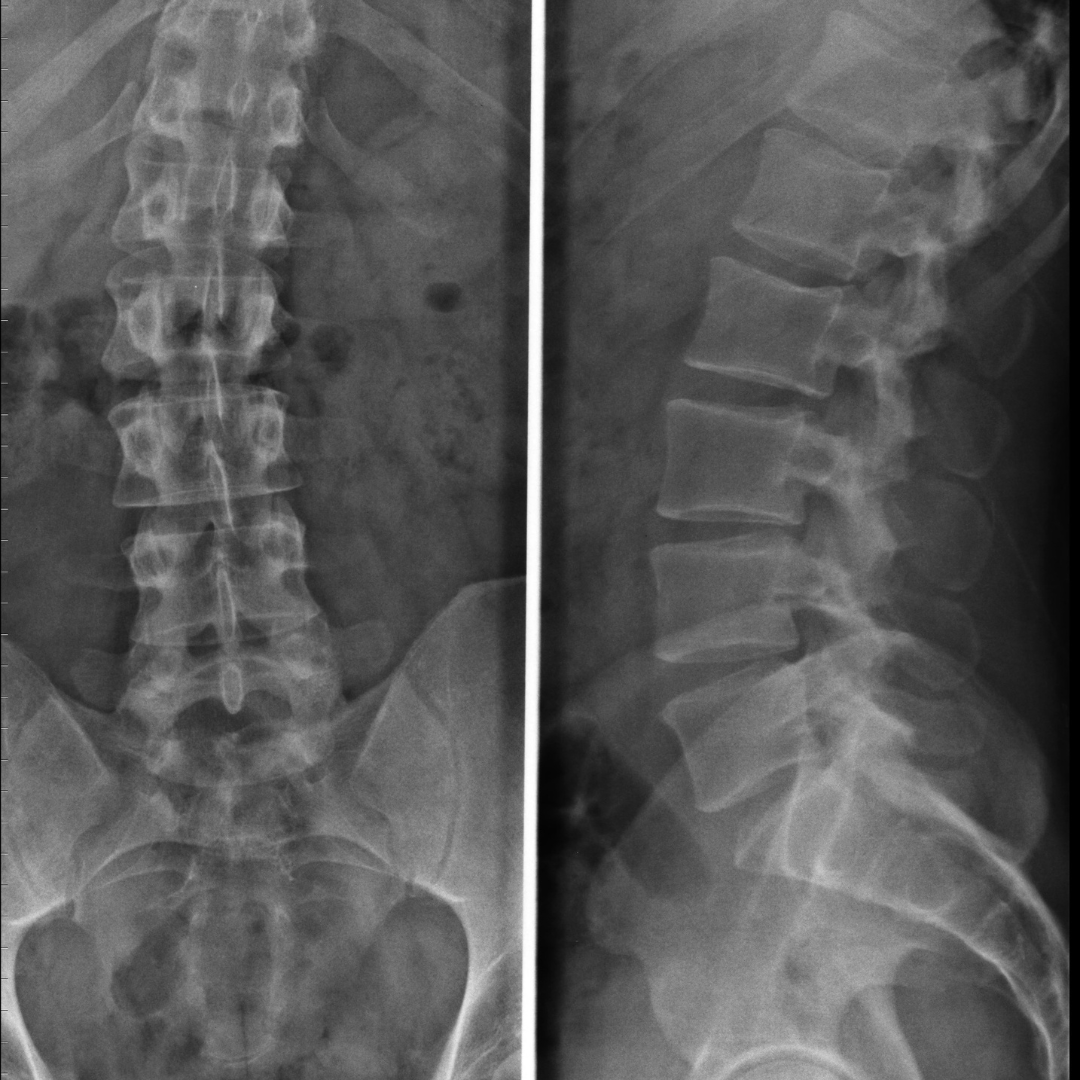

Interpretarea imagisticii coloanei vertebrale și corelarea clinică

Un curs practic care te învață cum să interpretezi RMN-ul, CT-ul și radiografiile coloanei vertebrale și cum să corelezi imaginile cu tabloul clinic al pacientului.

Lecția 3 – Hernia de disc lombară

Lecția 4 – Degenerarea discală și modificările vertebrale: cum le interpretezi practic

Lecția 5 – Stenoza de canal lombar: imagine, simptom, decizie terapeutică